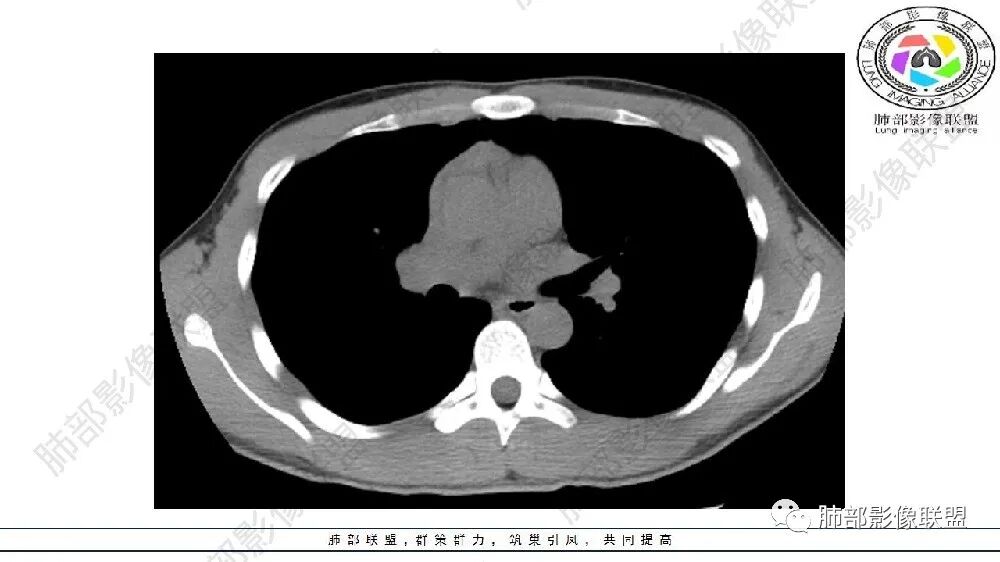

左肺下叶多发大小不等囊腔伴周围磨玻璃影,可见血管增粗,似与胸主动脉相连,考虑肺隔离症,鉴别CPAM。

左肺下叶病变气体潴留,血管增粗,体积缩小,慢性炎遗留表现,考虑局部反复感染,气道通畅,考虑血管病变,肺静脉畸形,肺隔离症?

左肺下叶多发囊腔、斑片、索条(粗大扭曲的血管?)降主动脉左侧有血管影?首先考虑肺隔离症,建议增强扫描,鉴别囊腺瘤样畸形

左肺下叶多发囊腔,粗大血管影,隔离征可能,鉴别气道畸形。

年轻男性,左肺下叶肺动脉明显增粗特点(与对侧比较,降主动脉旁胸膜下分布粗大血管征、左肺下叶肺气囊腔和磨玻璃影,首选肺隔离征,与血管畸形鉴别,病理生理特点:体循环异常分支(压力高)与左肺下叶肺动脉成异常交通。血管血流倒灌左肺下叶表现。

青年男性,左肺下叶多发囊腔伴磨玻璃影,并见增粗血管影,考虑肺隔离症。